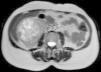

A ecografia renal demonstrou a presença de uma massa bem delimitada no pólo inferior do rim direito. Para esclarecimento da natureza e relação da massa procedeu-se à realização de uma ressonância magnética nuclear renal, que mostrou tratar-se de uma massa bem delimitada, macronodular, com 85mm de maior diâmetro, expressão radiária e cicatriz necrótica central com captação intensa de contraste, sugestiva de oncocitoma renal (Figuras 1 e 2).